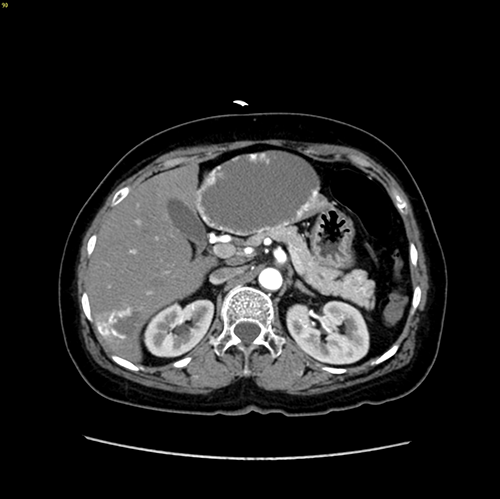

肝血管瘤--左肝外侧叶切除